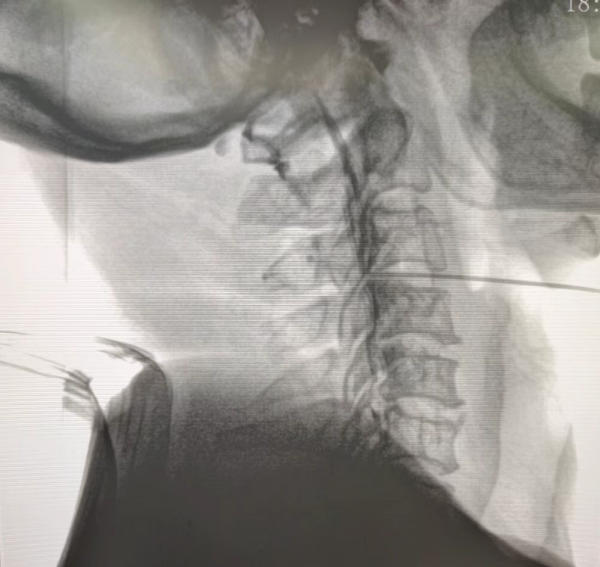

颈椎间盘射频消融联合胶原酶化学溶解术后